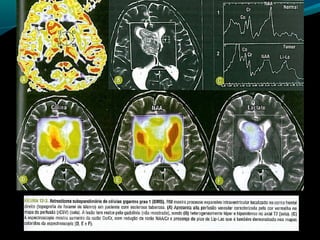

Astrocitoma subependimário de

células gigantes

TC:

Próximo ao forame de Monro (mas existe localização

atípica);

Expansiva e >1,5cm;

Iso ou hipodensa; pode ser heterogênea e apresentar

calcificações;

Realce intenso pelo contraste;

RM:

Baixo sinal em T1;

Alto sinal em FLAIR e T2 (ou heterogêneo se

hemorragia ou calcificações);

Regra: realce intenso e difuso pelo Gd;

RM:

Geralmente sem disseminação pelo LCR;

Aumento de Co/Cr

Redução de NAA/Cr

Picos de lactato;

Aumento da perfusão;

Paciente com CET RM

Se suspeita: controle anual por RM:

Crescimento e/ou aumento do realce de lesão próxima

ao forame de Monro  neoplasia;